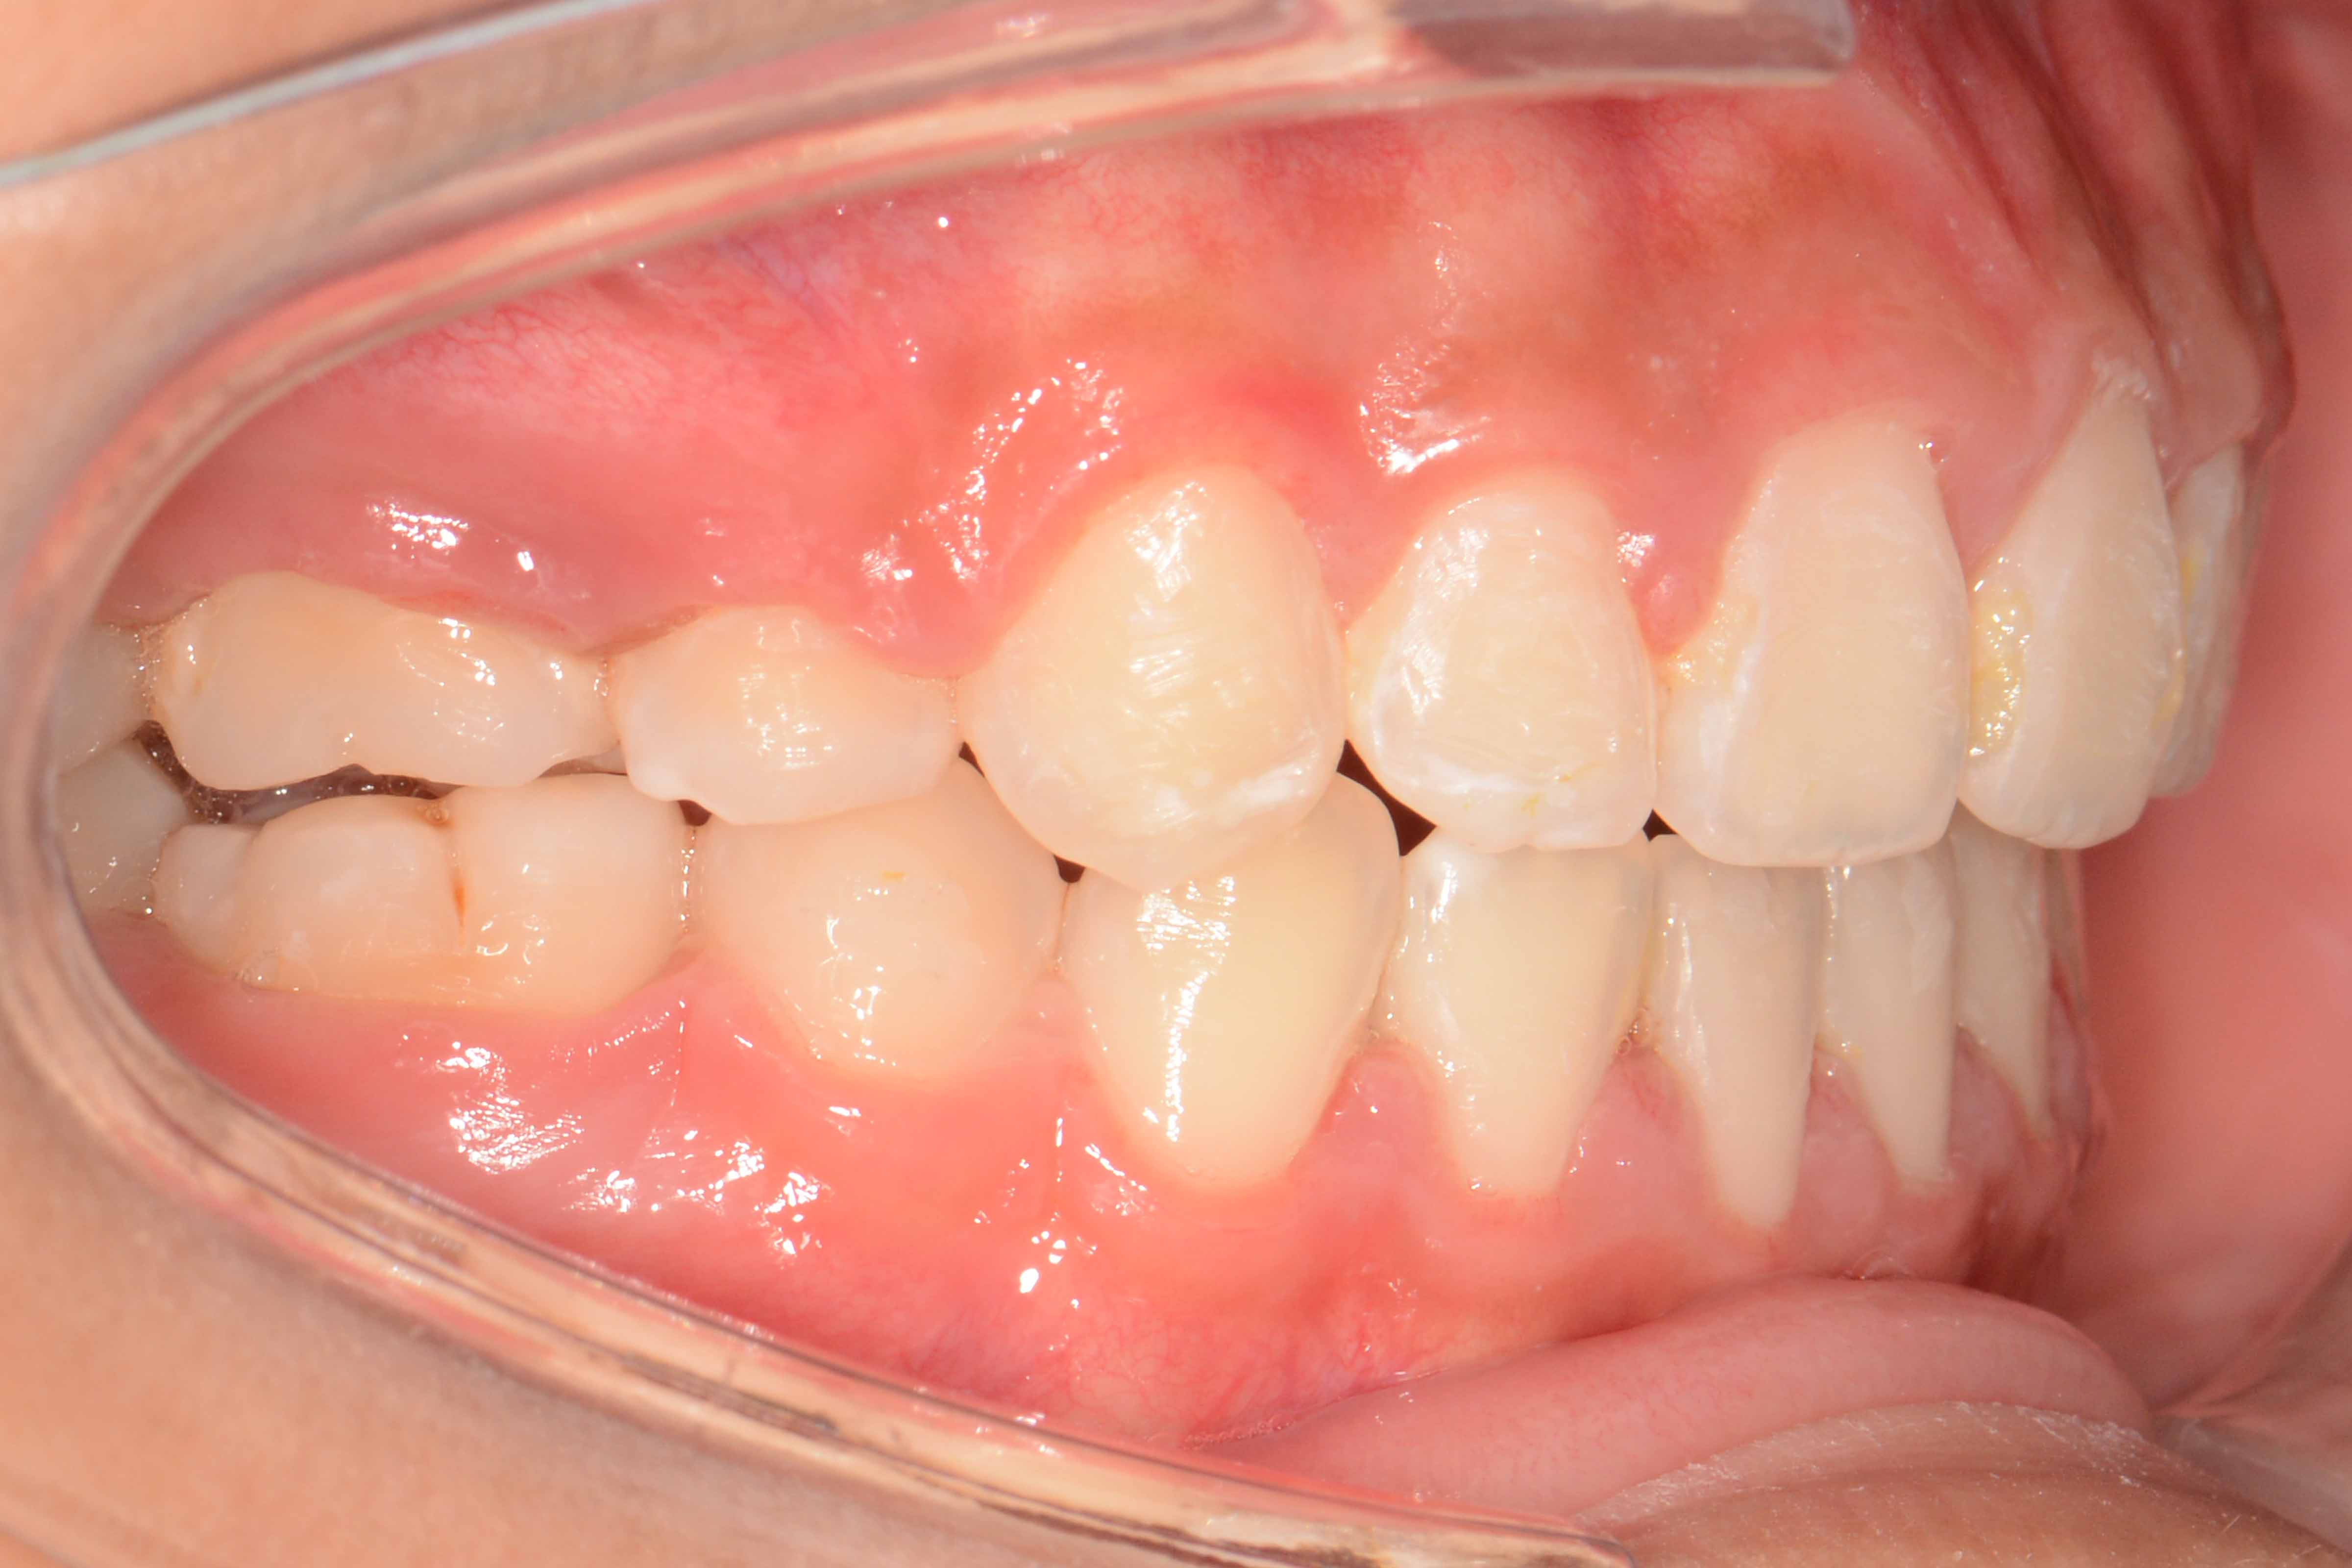

患者:14岁女性

主诉:前牙咬不住,进食不便

前牙区开颌3mm

诊断:安氏II类错颌畸形  开颌

矫治后: